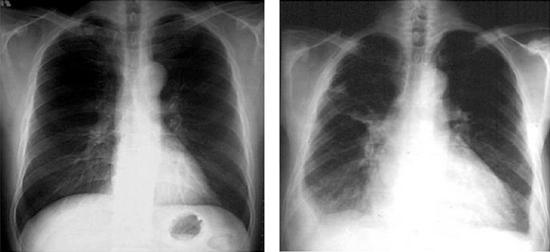

■심부전의 진단과 치료 방법 심부전을 진단하는 데에는 여러 가지 검사 방법이 있지만, 심장 초음파검사를 하면 심장근육과 심장판막이 어떻게 작동하는지 알려주고 심장이 뛰는 모습과 심장에 문제가 있는 부위를 알 수 있다. 심부전 환자를 진단하는데 있어 심장 초음파는 가장 핵심적인 검사 방법이다. 심부전의 치료에는 다음과 같은 방법들이 있다. ① 약물요법 심부전 환자는 일반적으로 약물 치료를 먼저 받는다. 심부전을 일으킬 수 있는 원인 질환이 있으면, 원인 질환을 치료하는 것이 원칙이다. 대부분의 환자에서 정상 심장 기능을 유지하기 위해서는 규칙적이고 장기적인 약물 치료가 필요한 경우가 많다. ② 수술요법 만약 심부전의 원인 질환이 심장의 구조적인 문제, 즉 심장판막 질환이거나 관동맥이 막힌 경우에는 수술적 치료가 필요할 수 있다. ③ 식사요법 심부전 환자에 대한 식사요법은 심장의 부담을 최소화하고 심근의 수축력을 올리는 것을 목적으로 한다. 과식은 심장에 부담을 주므로 피하고, 식사를 소량씩 나누어 섭취하도록 한다. 또한 과도한 비만은 그 자체가 심장에 부담을 주므로, 적절한 체중을 유지하는 것이 좋다. ·염분 제한염분은 몸속에서 수분을 붙잡고 있다. 몸속에서 늘어난 수분으로 인하여 심장은 더 많이 펌프질을 해야 하기 때문에 심부전 환자의 증상을 악화시킬 수 있다. 심부전 환자는 하루 염분 섭취를 5g 미만으로 제한하고 있다. 염분이 많은 음식을 피하고 싱겁게 먹어야 한다. ·수분 제한 체내의 많은 물은 심장을 더 피곤하게 만든다. 심부전 환자는 하루에 1.5~2ℓ로 수분 섭취를 제한해야 한다. ·고지방·고콜레스테롤 음식 제한 수분과 염분 제한 외에도, 심부전 환자는 고지방·고콜레스테롤 음식을 제한해야 한다. 이러한 음식들은 고지혈증 등과 같은 관상동맥 질환을 유발시켜 심부전의 원인이 되거나 증상을 악화시킬 수 있다. ④ 운동요법 예전에는 심부전 환자를 치료하는데에 무조건 안정 상태만을 권유하였지만, 최근에는 오히려 적절한 운동요법이 환자의 상태를 호전시키고 삶의 질을 높일 수 있다고 하여 점차 권장하고 있다. 심부전 환자는 대체로 운동 능력이 많이 떨어져 있으므로, 천천히 점진적으로 운동량을 증가시키는 것이 좋다. 따라서 격렬한 운동보다는 일상생활에서 손쉽게 할 수 있는 걷기운동부터 시작하는 것이 좋다. ■‘건강 맨’ 자신하다 심부전에 걸린 김 씨의 경우 다음은 심부전을 경험한 중년 남성 김모 씨에 대한 이야기이다. 65세인 이 남성은 젊었을 때 아마추어 레슬링 선수였을 정도로 건강에는 누구보다도 자신이 있던 사람이었다. 그런데 5년 전부터 혈압이 높다는 얘기를 들었으나, 증상이 없고 젊었을 때의 건강을 자신하면서 자신의 혈압에 관심을 가지지 않았다. 친구들을 만날 때에도 과거 자신의 건강을 자랑하면서 과음을 하게 되고 지속적으로 흡연도 하였다. 그러나 내원 한 달 전부터 운동할 때 호흡 곤란과 다리가 부어 오르는 증상으로 심장내과 외래를 방문하였다. 내원 당시 혈압은 180/90mmHg였고, 흉부 X-선상에 심장이 정상보다 심하게 커져 있었으며, 맥박도 불규칙하였다. 심전도상 심방세동이라는 부정맥 소견을 보였다. 심장 초음파검사 결과 심장 기능이 현저히 감소되어 정상인의 1/2밖에 되지 않았다. 김 씨는 심장내과 의사로부터 고혈압에 의한 중증 심부전이라는 진단을 받고, 그 동안 건강을 챙기지 못한 것을 후회하였다. 앞으로는 의사의 권고를 받아 규칙적인 생활과 혈압 조절을 하기로 마음을 먹었다. 고혈압 약제를 정기적으로 복용하고, 고염분 식이습관을 고치면서 규칙적인 생활 습관을 유지하였다. 그렇게 1년이 지난 후 김 씨의 혈압은 정상으로 유지되고, 감소된 심장 기능도 정상으로 회복되어, 현재는 특별한 심부전 증상 없이 외래에서 추적 관찰 중이다